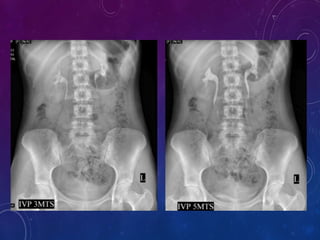

 1 minute film - 10x12

 5 minute film - 10x12

 1 minute film shows Nephrogram. This radiograph is often omitted has the

renal outlines are usually adequately visualized on 5 minute film

 5 minute film shows nephrogram, Renal pelvis, upper part of ureter.

 Compression band is now applied on Patients abdomen and the balloon is

positioned on anterior, superior iliac spine where cross the pelvic brim.

 This is to produce better pelviccalyceal distension.

 If compression band is applied a film is taken after 10 minutes , the film

should shows centered kidneys to demonstrate distended collecting system

and proximal ureter.